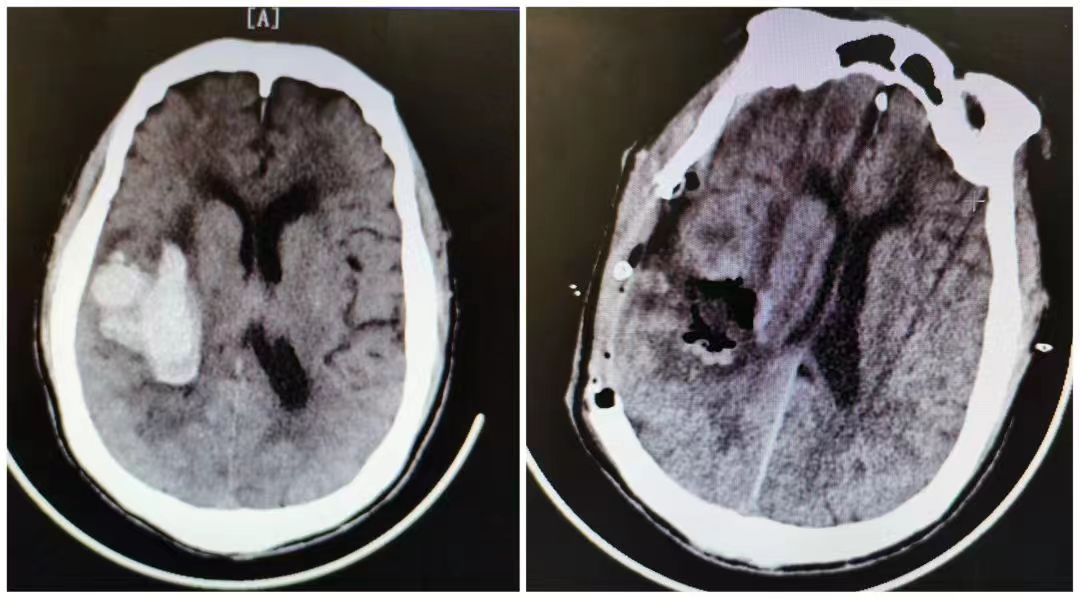

患者朱某,今年61岁,因突发言语不利并伴左侧肢体偏瘫1天,在家人陪同下来到紫阳县人民医院接受治疗。入院后,经头颅CT检查,朱某右侧基底节区脑出血,出血量约59ml。骨科医务人员立即为其予以止血、控制血压等对症治疗,复查CT后出血无明显增加。经与患者家属充分沟通,在邵华明主任与紫阳县人民医院骨科漆刚、杜义两名医师的通力合作下,顺利为朱某实施了“全麻下行右侧基底节出血去颅骨瓣减压术+颅内血肿清除术”。术后复查颅脑CT见右侧基底节出血已清除。